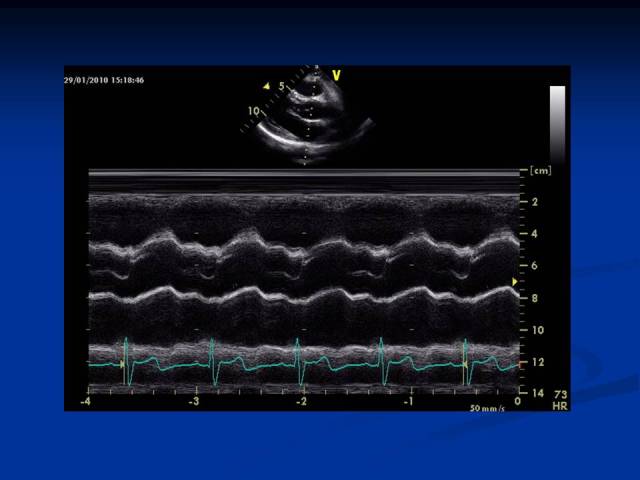

m型超声心动图

超声心动图和心衰(Ⅱ) 勿忘右心 那惊鸿的一瞥